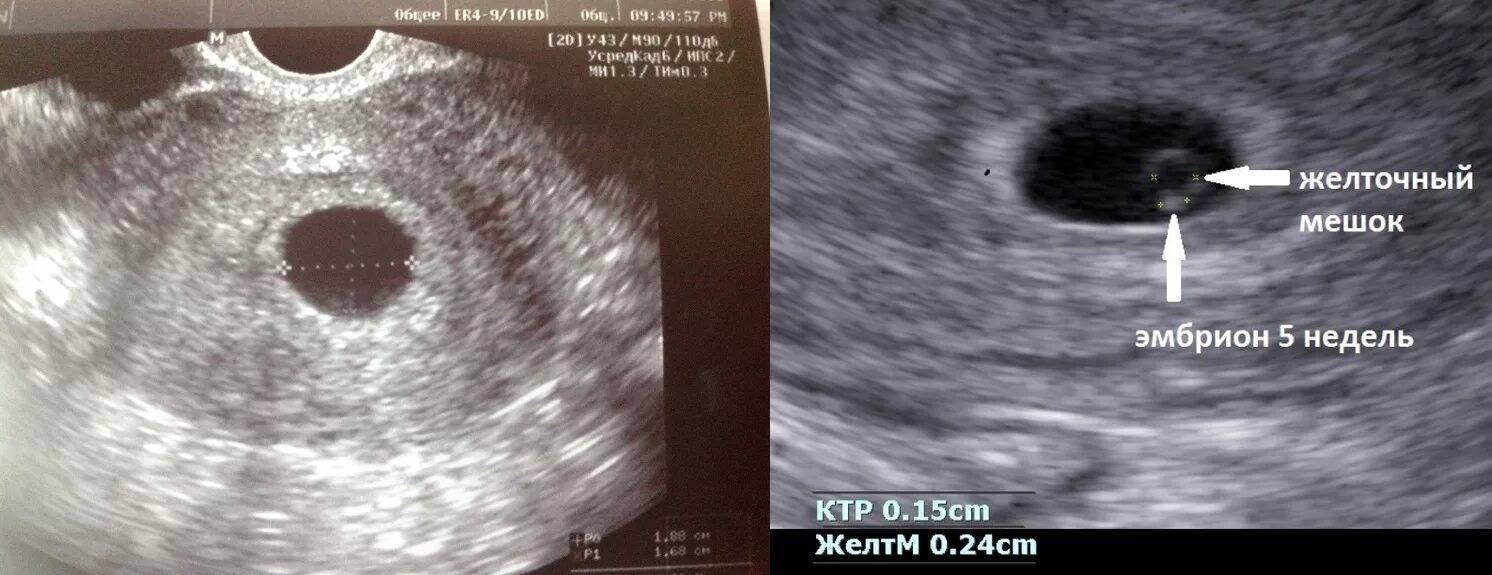

Желточный мешок 2 мм